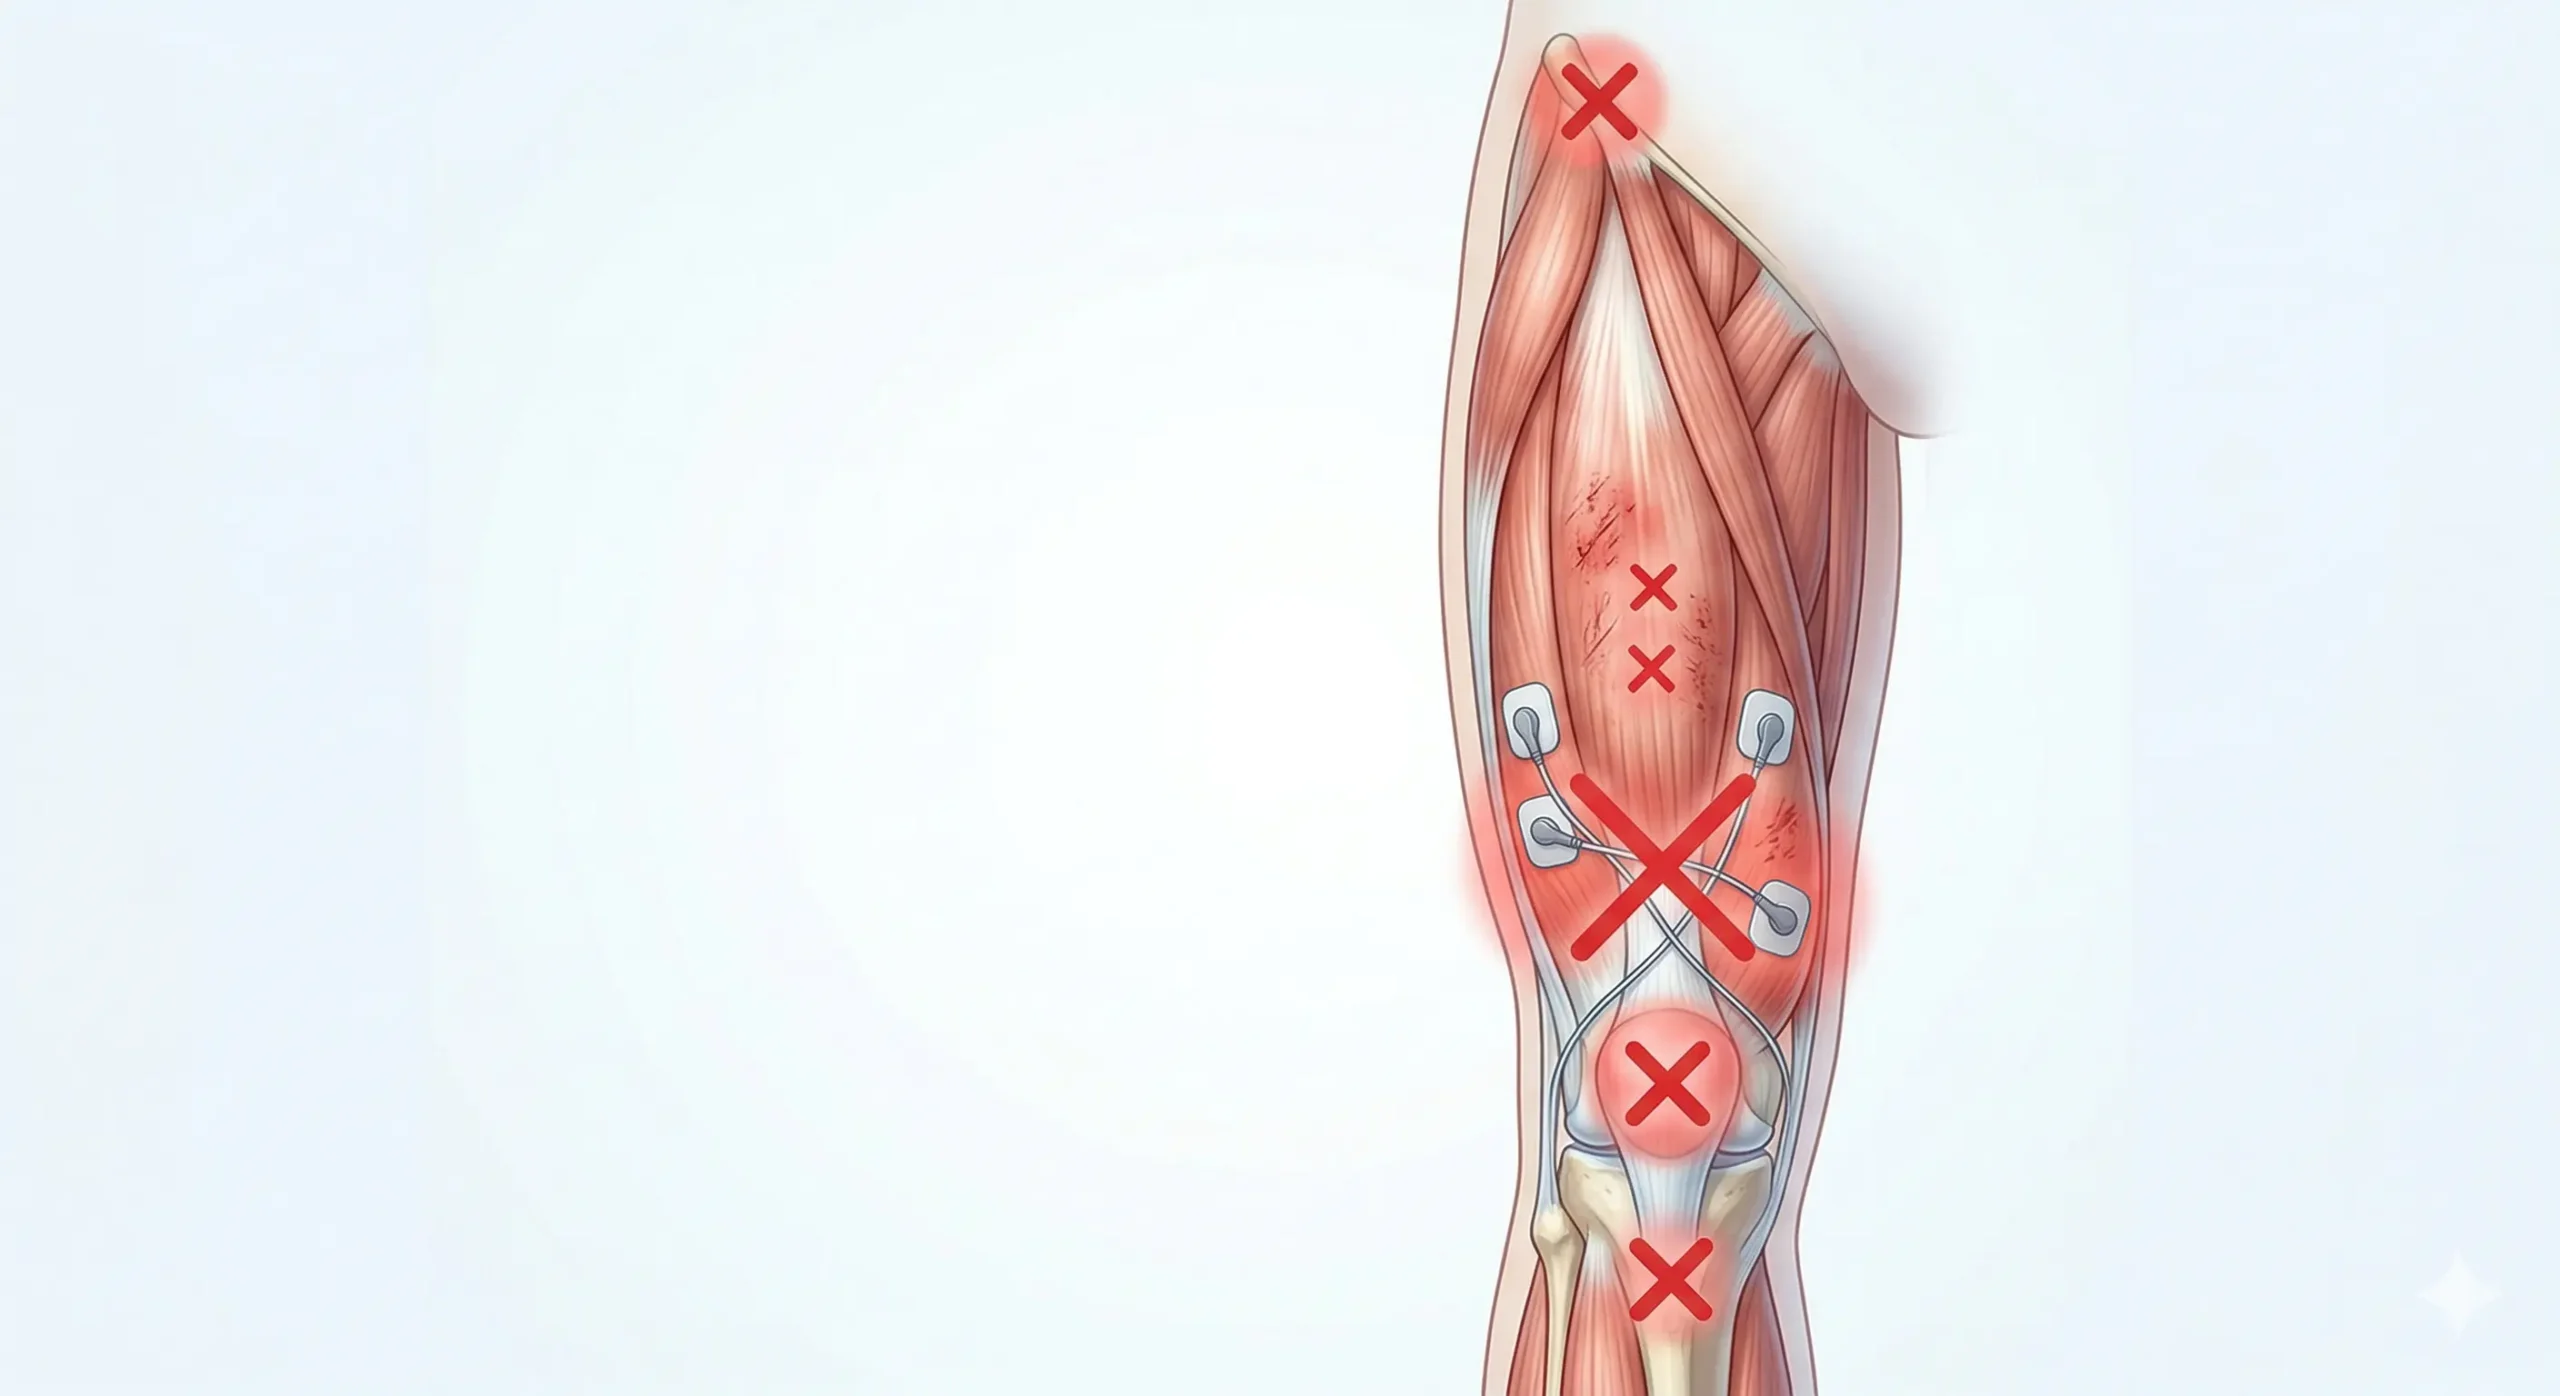

Dónde NO colocar el TENS en cuádriceps

- No coloques electrodos sobre la rótula.

- No pegues electrodos en la ingle ni demasiado cerca de zonas sensibles.

- No coloques electrodos sobre heridas, irritaciones, hematomas grandes o piel alterada.

- No bajes demasiado el montaje hacia el tendón rotuliano si el objetivo es el cuádriceps.

- No uses intensidad dolorosa o con quemazón como señal de eficacia.

- No confundas TENS con EMS si el programa provoca contracciones intensas y tu objetivo es solo aliviar dolor.

- No lo uses como única estrategia si hay dolor recurrente por carga mal ajustada.

- No uses TENS con marcapasos u otros implantes electrónicos sin valoración sanitaria.